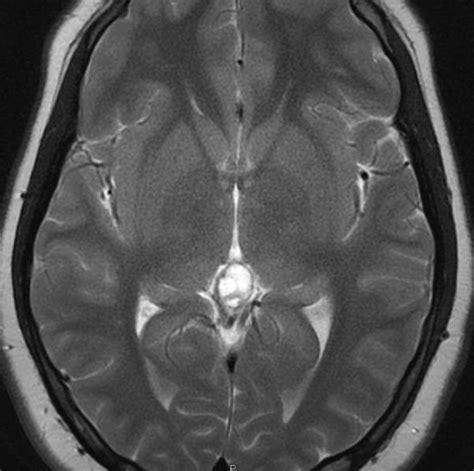

Diagnosing and Monitoring

In most instances, a Pineal Gland Cyst is discovered incidentally. Once identified, neuroradiologists evaluate the cyst using magnetic resonance imaging (MRI). The imaging helps determine the size, appearance, and whether the cyst is putting pressure on critical brain structures.

Appearance Smooth, thin-walled, and fluid-filled.

Growth Typically stable; they rarely grow or change over time.

Management Observation via follow-up MRI is the standard approach for small cysts.